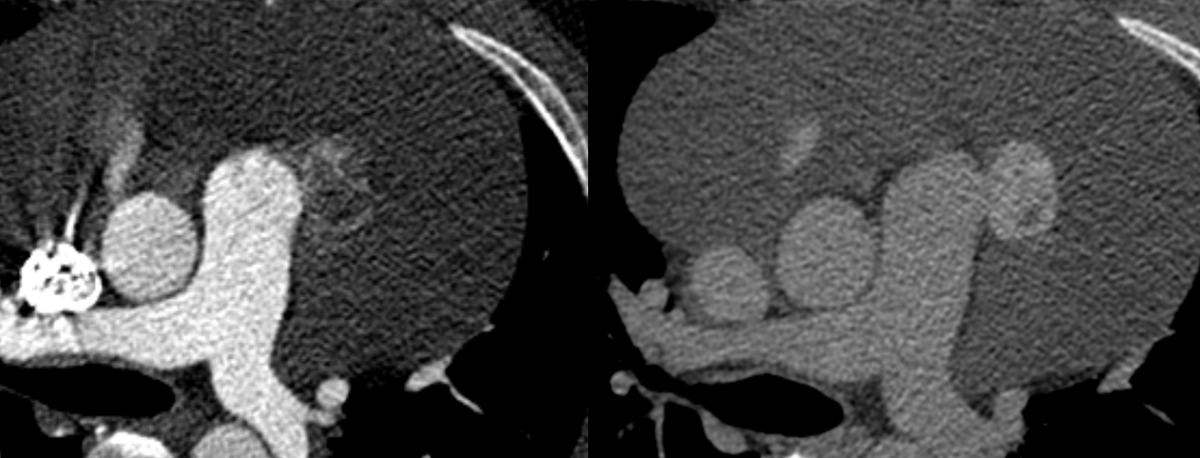

Tumors

Cardiac mass